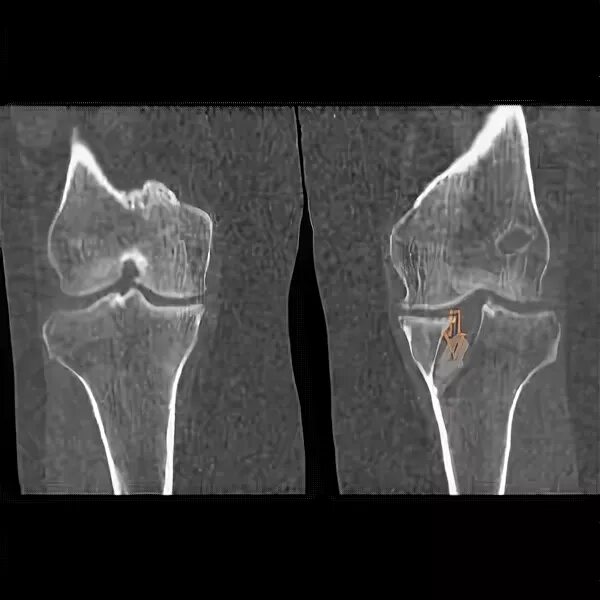

Деформирующий гонартроз коленных суставов 2 степени